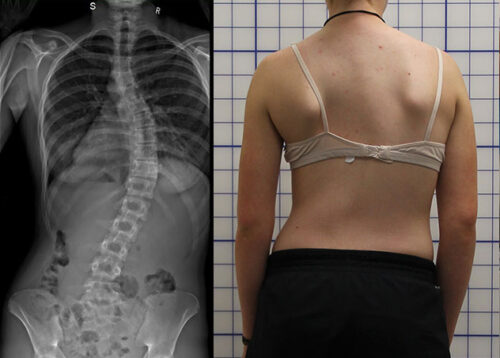

أخطر أنواع اعوجاج العمود الفقري عند الأطفال والمراهقين: كيف تعرفها وتحمي طفلك من المضاعفات يعاني العديد من الأطفال والمراهقين من اعوجاج العمود الفقري، المعروف طبيًا بالجنف، وهو انحناء جانبي للعمود الفقري قد يصاحبه دوران

هل اعوجاج العمود الفقري له علاج؟طرق وأسرار التغلب على الجنف يعاني العديد من الأطفال والمراهقين من اعوجاج العمود الفقري، المعروف بالجنف، وهو انحناء جانبي للعمود الفقري قد يصاحبه التواء في الفقرات. عند تشخيص الطفل